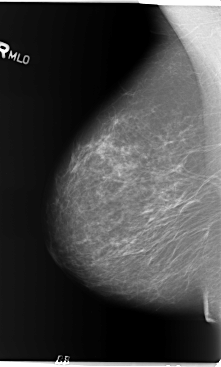

B_3154_1.RIGHT_MLO

LEFT_MLO LINES 5792 PIXELS_PER_LINE 3560 BITS_PER_PIXEL 12 RESOLUTION 50 OVERLAY

RIGHT_MLO LINES 5864 PIXELS_PER_LINE 3528 BITS_PER_PIXEL 12 RESOLUTION 50 NON_OVERLAY